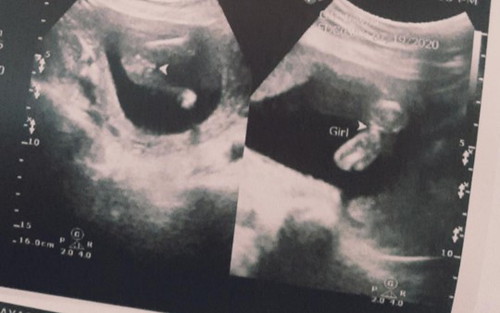

Baby's gender

Hi mga mamshi! this ultrasound was taken 2 weeks ago, when I was 16 weeks. sabi po kasi nung nag ultrasound hindi pa sya 100% sure na baby girl and bumalik ako before bumili ng gamit ni baby. Sa tingin nyo po sure na baby girl na?? Medyo excited din po and nakabili na ng konting things for my baby. Planning to visit again sa clinic after a week gusto ko lang po mag ask baka may same case ako dito. ?